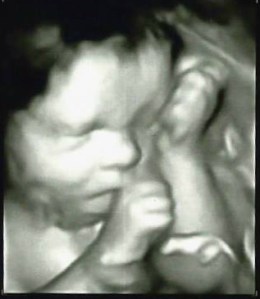

You know what is hard? Coughing up the dough needed to publish the most professional product possible. In the grand scheme of things, $300 isn’t really that big of an investment. But when you’ve got a baby on the way and are living off only one stable income, the idea of parting with any chunk of cash is insomnia-inducing at best.